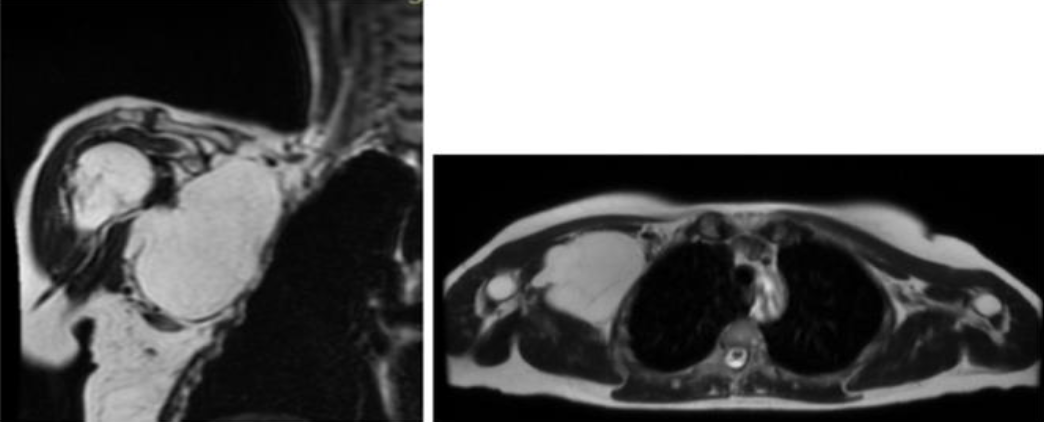

Lipomas are benign mesenchymal tumors and represent the most common type of soft tissue tumors [1]. Lipomas can occur at any age, but they are most commonly found in individuals between 40 and 70 years of age. There does not appear to be a significant gender predisposition. These tumors can arise in various anatomical locations, with the most common sites being the thigh, followed by the shoulder [2]. The etiopathogenesis of lipomas remains not fully understood. Some researchers suggest a genetic predisposition as a key factor in their development, while others hypothesize that trauma may play a central role [3]. Additionally, studies have found an association between lipomas and conditions such as diabetes mellitus and dyslipidemia [4]. Diagnosis of lipoma is typically made through a physical examination. Imaging studies (such as CT or MRI) or a biopsy may be needed to confirm the diagnosis and assess the nature of the lesion. Is important to consider differential diagnosis with malignant formations. A lipoma grows slowly and is benign. A liposarcoma is a malignant tumor that also originates from fat cells. Liposarcomas grow rapidly and they can invade surrounding tissues and spread to other parts of the body. Liposarcomas are rarer and more aggressive than lipomas [5]. The differential diagnosis is typically clinical, supported by ultrasound or Magnetic Resonance Imaging (MRI). Lipomas on MRI typically have well-defined, regular margins and homogeneous in appearance. Liposarcomas, on the other hand, tend to have irregular or indistinct margins and may invade surrounding tissues. A biopsy is rarely required, but may be performed if the tumor exhibits atypical features. In cases where lipomas cause pain and functional limitations, surgical removal may be necessary. However, their removal is not always straightforward. In some cases, lipomas can compress or infiltrate adjacent nerve structures. During surgical removal, it is important to avoid causing iatrogenic damage. Therefore, it is crucial to assess the potential involvement of nerves before surgery using electromyography and sometimes during the surgery with electrostimulation. In this study, we analyzed ten cases of atypical shoulder lipomas. All patients presented with symptomatic lipomas, resulting in pain, functional limitations, reduced range of motion (ROM) in the shoulder and impact on quality of life. All patients were treated with surgical excision, which remains the treatment of choice for symptomatic lipomas, as well as for cosmetic reasons.